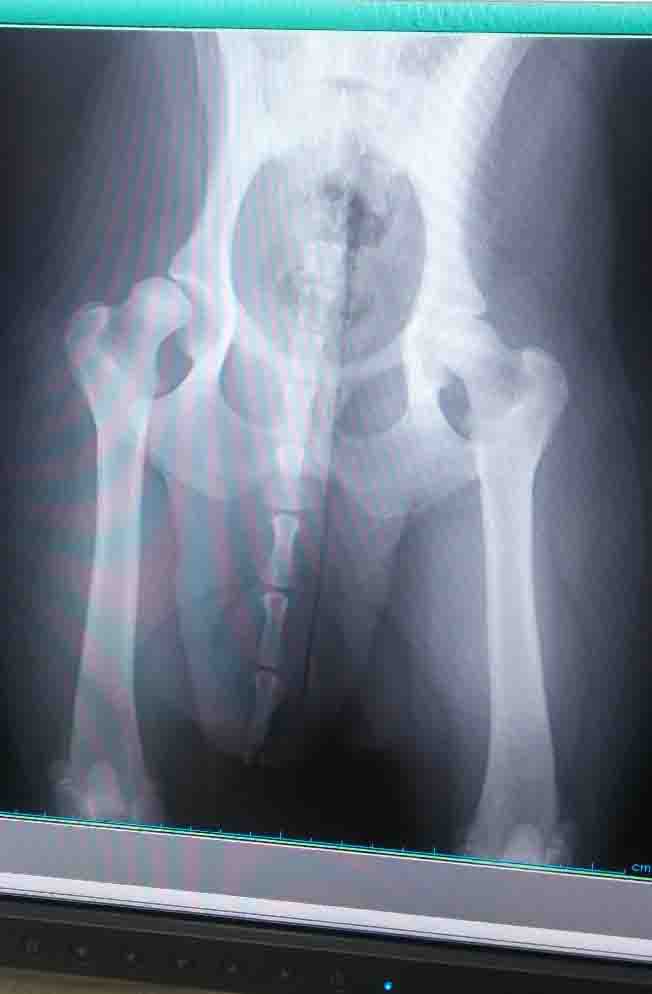

重度

(右43 左5)

右側の受けは表面がギザギザしていてなめらかでなく、骨頭を受け止められないくらいに浅い

左足は受け側が骨頭をしっかりホールドしているのが分かる、受け側の張り出しは正常、骨頭も丸くきれい